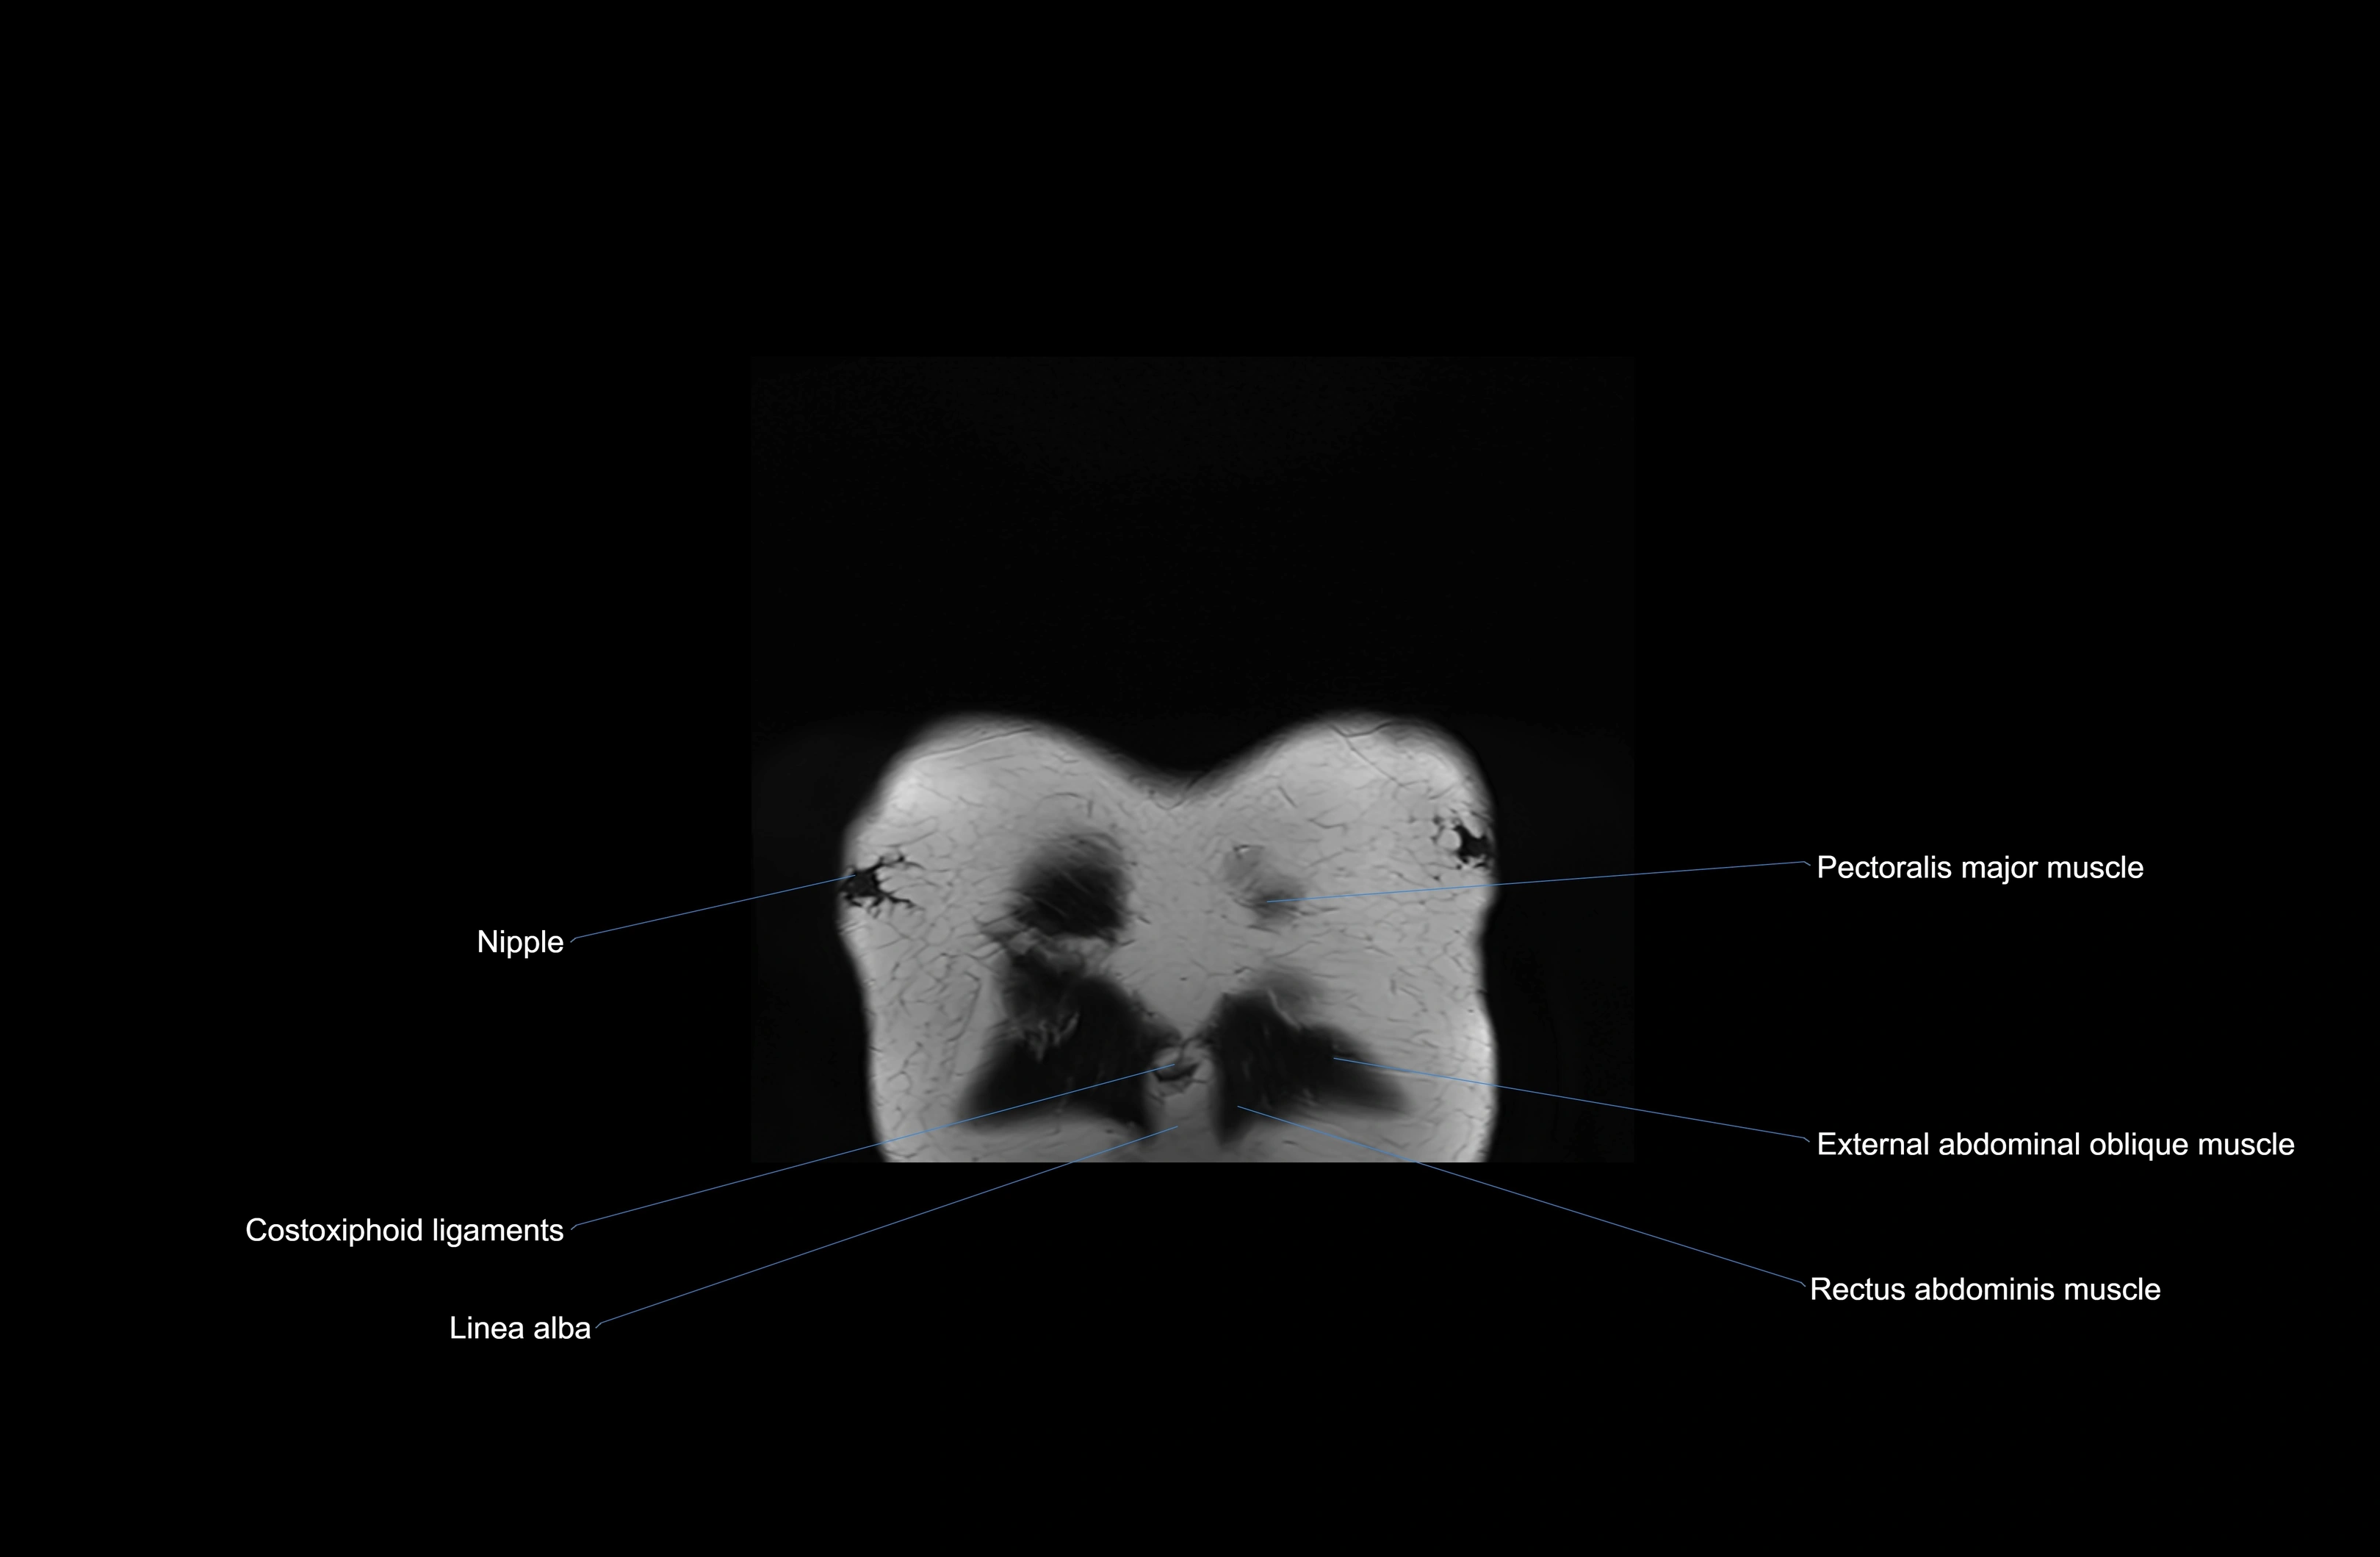

MRI images